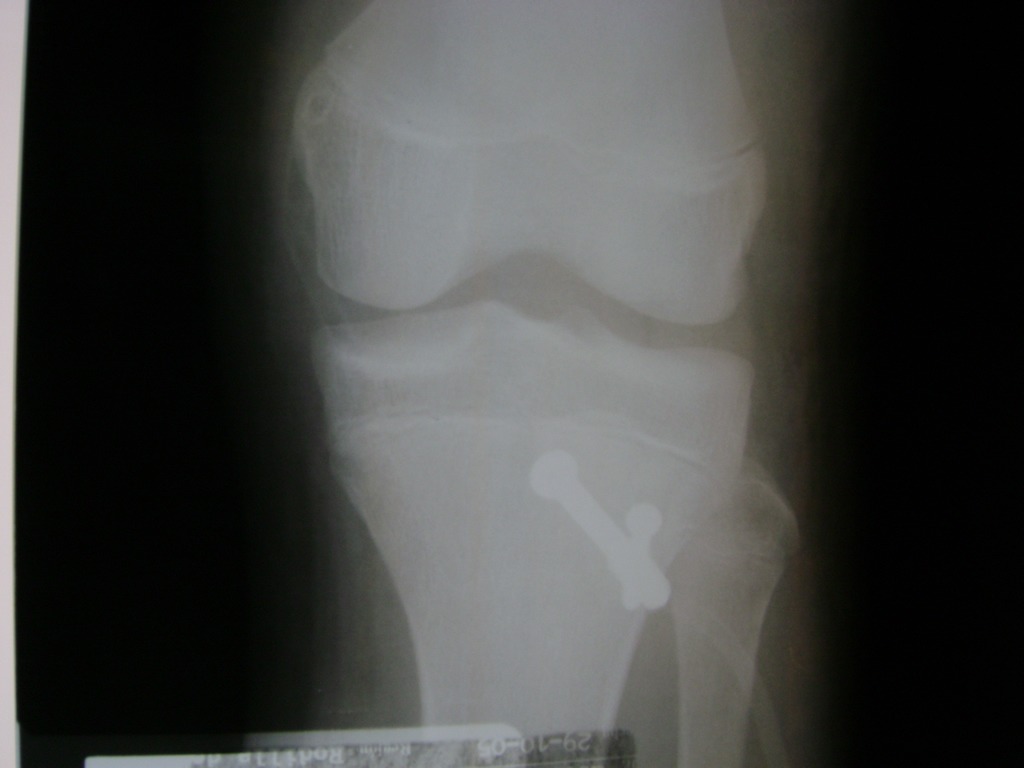

La artroscopia de rodilla es un cirugía en el cual la estructura interna de la articulación es examinada ya sea para realizar un diagnostico o para realizar un tratamiento, este procedimiento se realiza utilizando un instrumento parecido a un pequeño tubo llamado artroscopio.